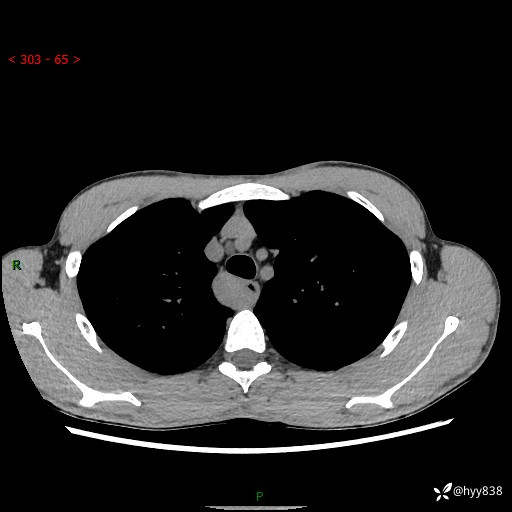

年轻男性,发现后纵隔占位1周余。征象简单,难在定位---结果公布~

现病史:患者于1周前体检行检查发现后纵隔占位,患者平素无明显咳嗽咳痰,无心慌、胸闷、胸痛、呼吸困难、低热、盗汗,无头痛、头晕,无腹痛、腹胀等不适。现患者欲求进一步治疗,遂来我院就诊,以“纵隔占位”收入我科。 患者自起病以来,精神可,睡眠可,饮食可,大小便正常,体重无明显改变。

胸部CT平扫+增强